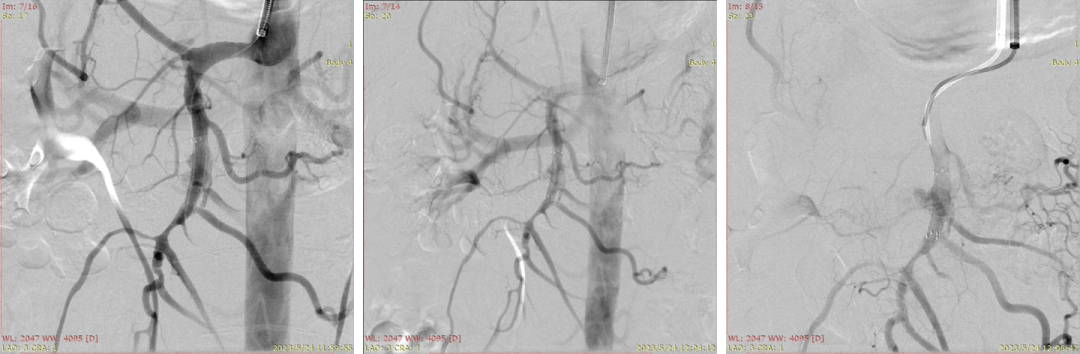

20230524DSA夹层动脉瘤

20230524DSA:VB支架植入

20230524DSA:仍有造影剂进入假腔

20230524DSA:再次送入VB